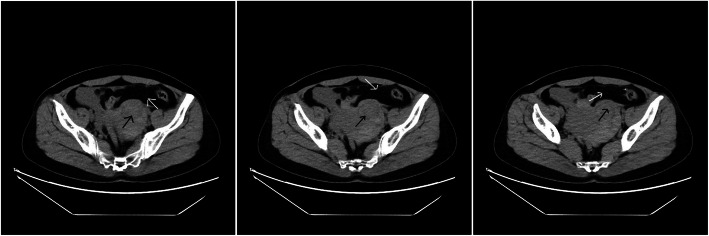

On laboratory examination, leukocyte count 14,880/mm3, hemoglobin 10.2 g/dl, and serum β hCG > 10,000 mIU/ml were detected. CT scan revealed the presence of a low-density shadow in the left accessary area and a large amount of bloody effusions in the pelvic cavity (Fig. 1).

Fig. 1.

Preoperative CT scan of the abdomen with arrow mark showing adnexal mass (black) and bloody pelvic effusions (white)